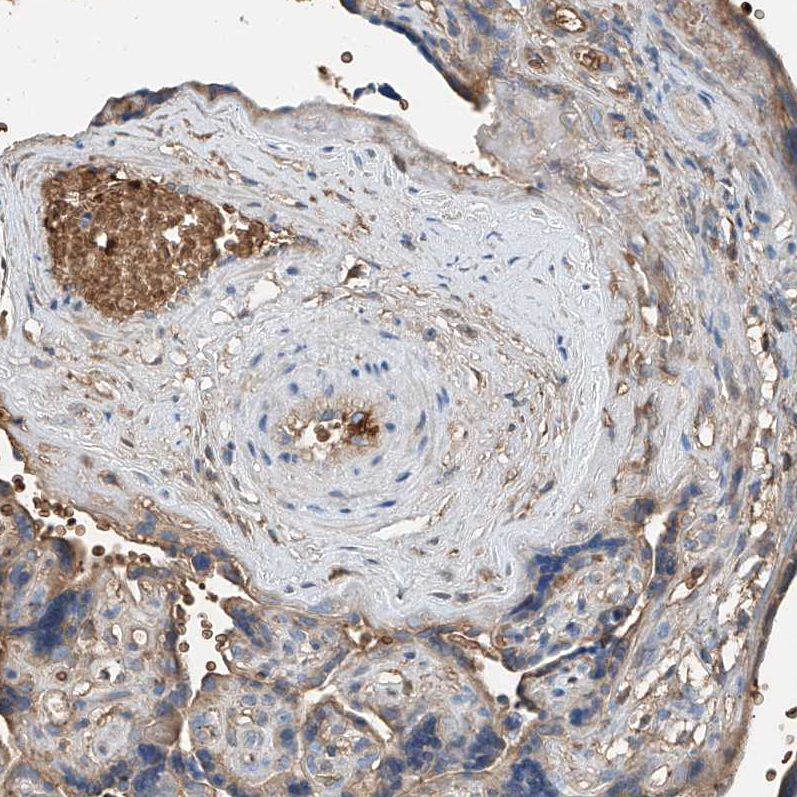

Immunohistochemical staining of human placenta shows moderate cytoplasmic positivity in trophoblastic cells.